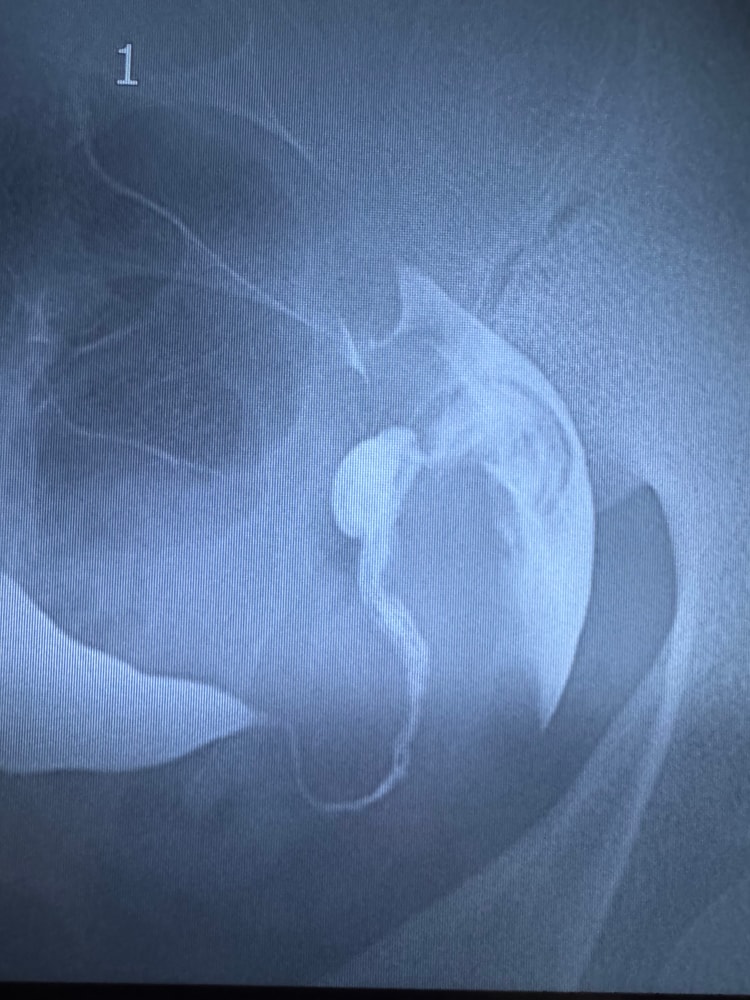

Девочки, подскажите . У меня спкя, отсутствие овуляции, отсутствие своего цикла. На стимуляции летрозолом в декабре случилась Б, но увы вб. Удалили трубу. Решила я сделать гсг, проверить вторую трубу. Заключение:Полностью проходима, но длинная, тонкая, извитая. Обошла нескольких врачей, одни говорят, что это просто особенность трубы, ничего страшного, беременеть можно. Другие говорят, что лучше не надо, это 100% опять вб. Надо лучше на эко.

Я не знаю уже кого слушать. На июль записалась еще к одному репродуктологу. Может быть у кого то была похожая ситуация? Я понимаю конечно, что это чужие истории, и у меня может быть все по-другому. Но все же. Может посоветуете что нибудь, или поделитесь размышлениями на эту тему. Фото снимков гсг приложу.